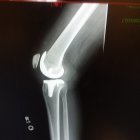

The titanium knee as of today. Replaced on the 15th, ripping pain for 7 days at least, then started to subside. 80% worst pain gone, still sore though.